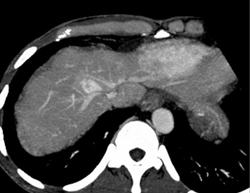

Islet Cell Involves the Portal Vein With Collaterals